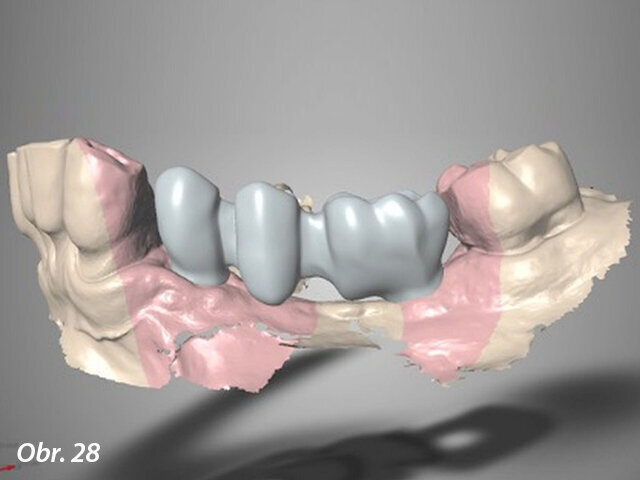

Kromě toho byla ve vestibulární oblasti implantátu v oblasti zubu 34 současně provedena augmentace za použití membrány Straumann Jason a kostního štěpu. Důvodem této horizontální augmentace byla tenká (méně než 1,5 mm) zbytková kost ve vestibulární oblasti (obr. 15). Kolagenní membrána byla stabilizována pomocí zirkonového vhojovacího abutmentu (RC ø 4,5 mm, výška 4 mm), zatímco pro implantát v oblasti zubu 36 byl našroubován titanový vhojovací abutment (RC ø 4,5 mm, výška 4 mm). Laloky byly uzavřeny umístěním jednoduchých stehů Vicryl 5/0 (obr. 16–20).